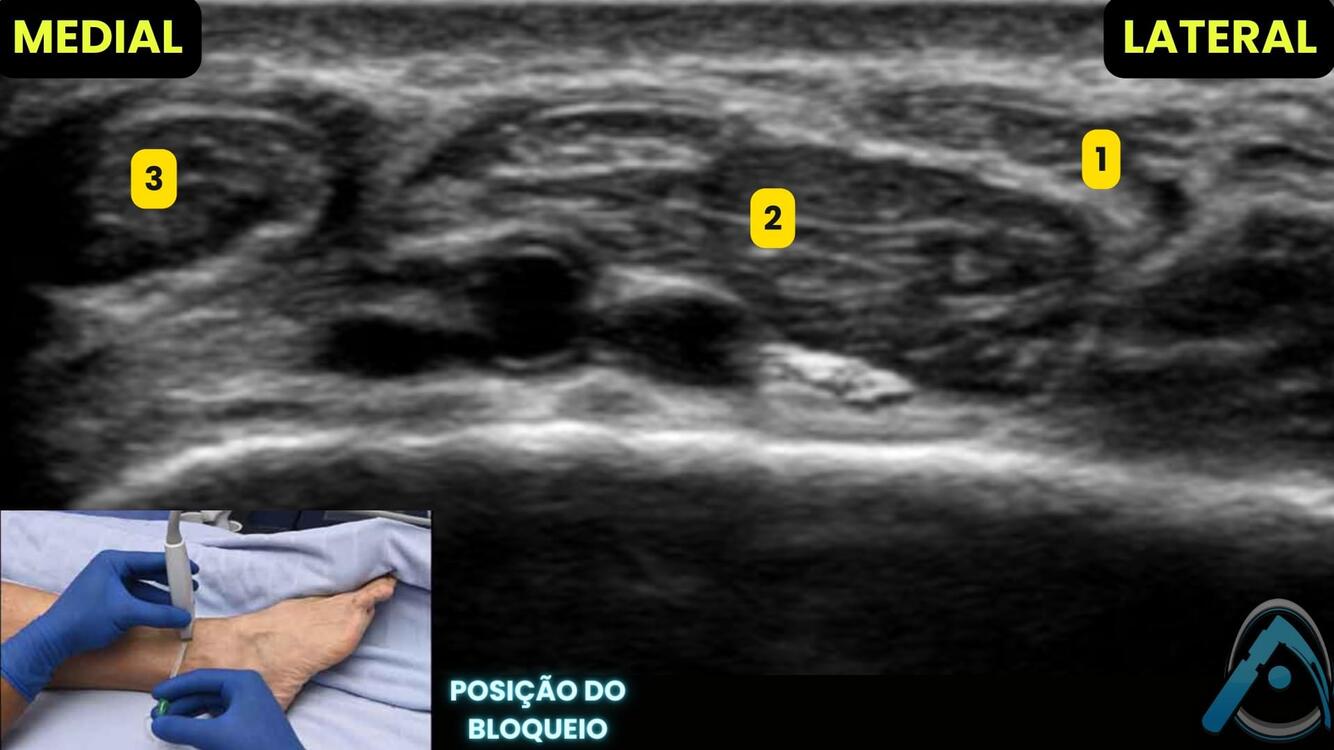

Realizando o bloqueio abaixo para analgesia de joelho, o que são as estruturas apontadas?

1 - nervo safeno;

2 - nervo para o vasto medial;

3 - artéria femoral;

4 - adutor longo

Veja as estruturas do **bloqueio do nervo safeno* no triângulo femoral distal: